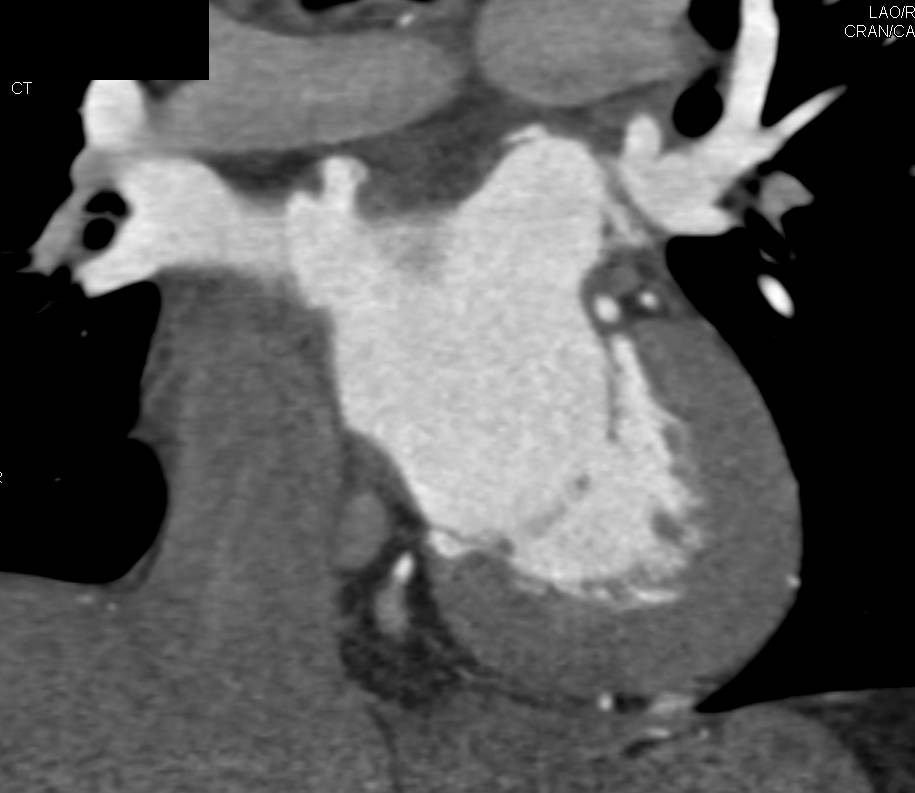

Pericardial Cyst in 3D